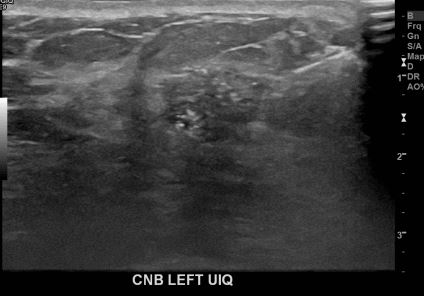

아산유외과개원후 646번째 유방암진단

상기환자 외부검사상 이상소견으로 내원하신 50대여성으로 좌측유방의 의심스러혹

조직검사시행해 유방암 진단되었습니다.